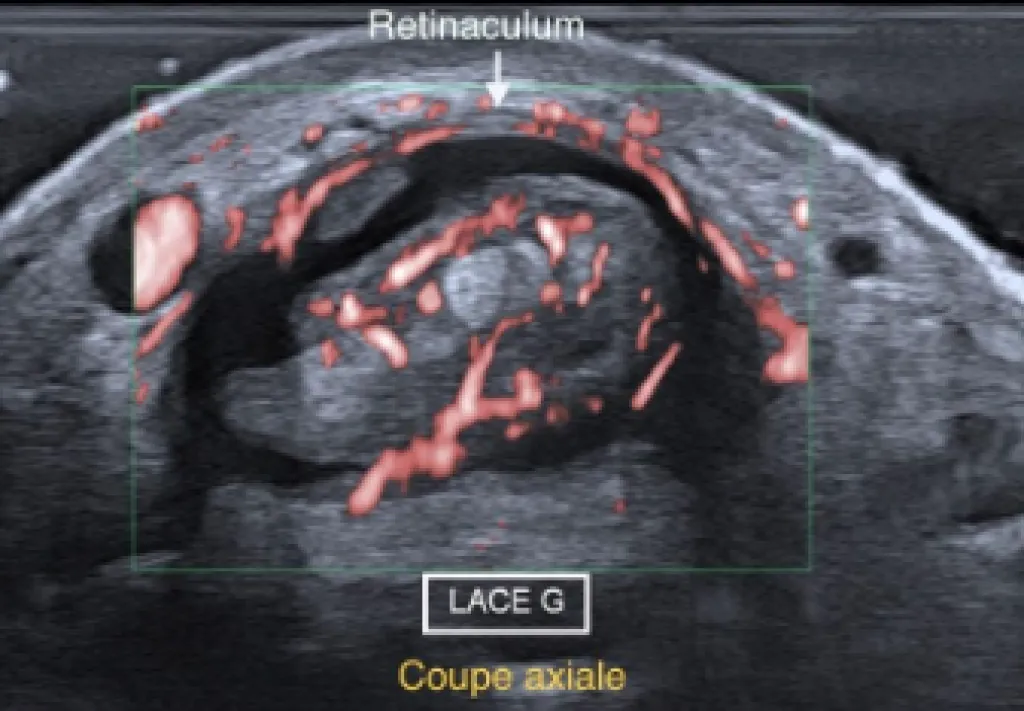

Test de Finkelstein positif L’examen échographique objectif un épanchement anéchogène de la gaine des tendons Long Abducteur et Court Extenseur du pouce (LACE) avec hypertrophie tendineuse d’aspect multifasciculé et hypervascularisé.On note un épaississement inflammatoire du rétinaculum entraînant...